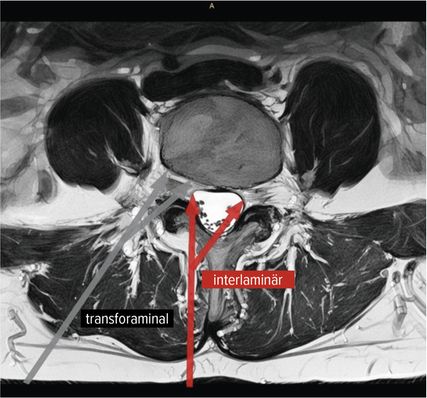

Der interlaminäre Zugang

Der interlaminäre endoskopische Zugang bietet Vorteile in den Segmenten L4/5 und L5/S1 aufgrund der Weite des Interlaminärfensters. Dem Chirurgen kommen dabei die Erfahrungen des offenen interlaminären Zugangs zugute, da die Ausrichtung des Sichtfeldes und anatomische Orientierung ident sind. Während der transforaminäre Zugang vorwiegend bei Diskektomien zum Einsatz kommt, hat die Entwicklung des IL-Zugangs das Indikationsspektrum erweitert. Zentrale Spinalkanalstenosen, Rezessusstenosen, aber auch die kontralaterale Foraminotomie sind mögliche Einsatzgebiete.11–13 Abbildung 2 illustriert die interlaminäre (roter Pfeil) und transforaminäre (grauer Pfeil) endoskopische lumbale Zugangstrajektorien (MRI-t2-gewichtet). Abbildung 3 zeigt das Kambin-Dreieck. Dieses weist die Form eines rechtwinkligen Dreiecks auf und wird durch die austretende Nervenwurzel (Hypotenuse), den Duralsack, den Processus articularis superior des Facettengelenkes und die Grundplatte (Basis) begrenzt. Es stellt eine sichere Landungszone für das Endoskop im Neuroforamen dar.